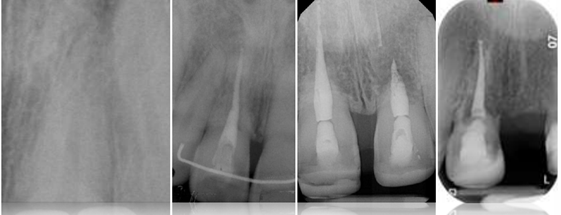

radiographic assessment prior to dx

2 angles (30 degrees mesial or distal beam shift)

or CBCT

Parallax – find out if resorption buccal, lingual or external/internal

* If resorption moves – external

* If fixate/centre in tooth – internal

Single biggest thing to aid dx – internal balloons out from internal aspect of canal

* Parallel lines of RCS lost (tramlines) = INTERNAL

* External = superimposition of resorption – can still see tramlines of pulp, internal aspect of RCS intact